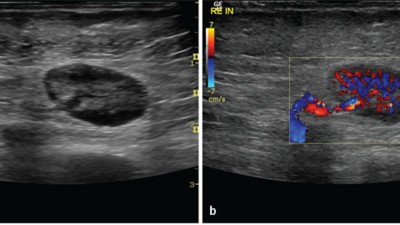

Ultraschall In Der Diagnostik Maligner Lymphome Springerlink

Abb 1 9 Seit 3 Wochen Persistierende Indolente Schwellung Am Linken Download Scientific Diagram